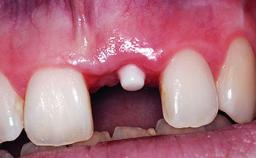

Replacement of a Compromised Upper Right Central Incisor: Hard- and Soft-tissue Augmentation, Late Placement of an RC Bone Level Implant

A 36-year-old male patient with a compromised maxillary central incisor was referred by his general dentist for consultation. The patient’s chief complaints were the gradual debonding of a temporary crown on the right central incisor and unsatisfactory esthetics due to an increasing diastema between the right central and lateral incisors. The patient reported a traumatic event some years previously, when a crown had been placed after root-canal treatment. The referring dentist wanted to provide a new crown restoration, but was concerned about the condition of the residual root. Anamnesis was negative for any other dental or periodontal pathology in the remaining dentition. The patient reported taking no medications: He was a smoker (10 to 15 cigs/day) and had realistic esthetic expectations.

Placement Protocol Early or late implant placement